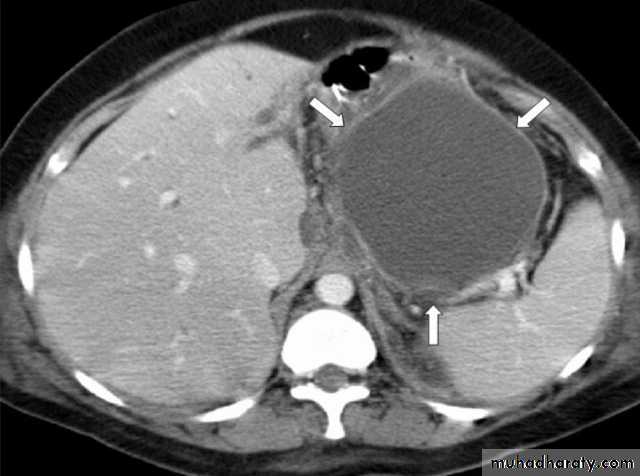

1. Acute fluid collections: occur early in the course of acute pancreatitis, are located in or near the pancreas and always lack a wall of granulation of fibrous tissue.

In about half of patients, spontaneous regression occurs.

In the other half, an acute fluid collection develops into a pancreatic abscess or pseudocyst

3. Acute pseudocyst: collection of pancreatic juice enclosed by a wall of fibrous or granulation tissue, occurring at least 4 weeks after onset of symptoms, is round or ovoid and most often sterile; when pus is present, lesion is termed a ‘pancreatic abscess’